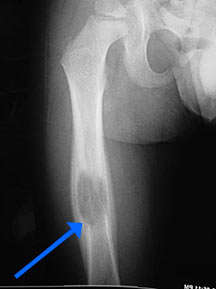

- May arise from any bone and any site within a bone (epiphyseal, metaphyseal, diaphyseal)

- Radiographically variable appearance: may appear benign (geographic) or malignant (permeative or moth eaten)

- Curettage and bone grafting for long bones and weight bearing bones at risk for fracture